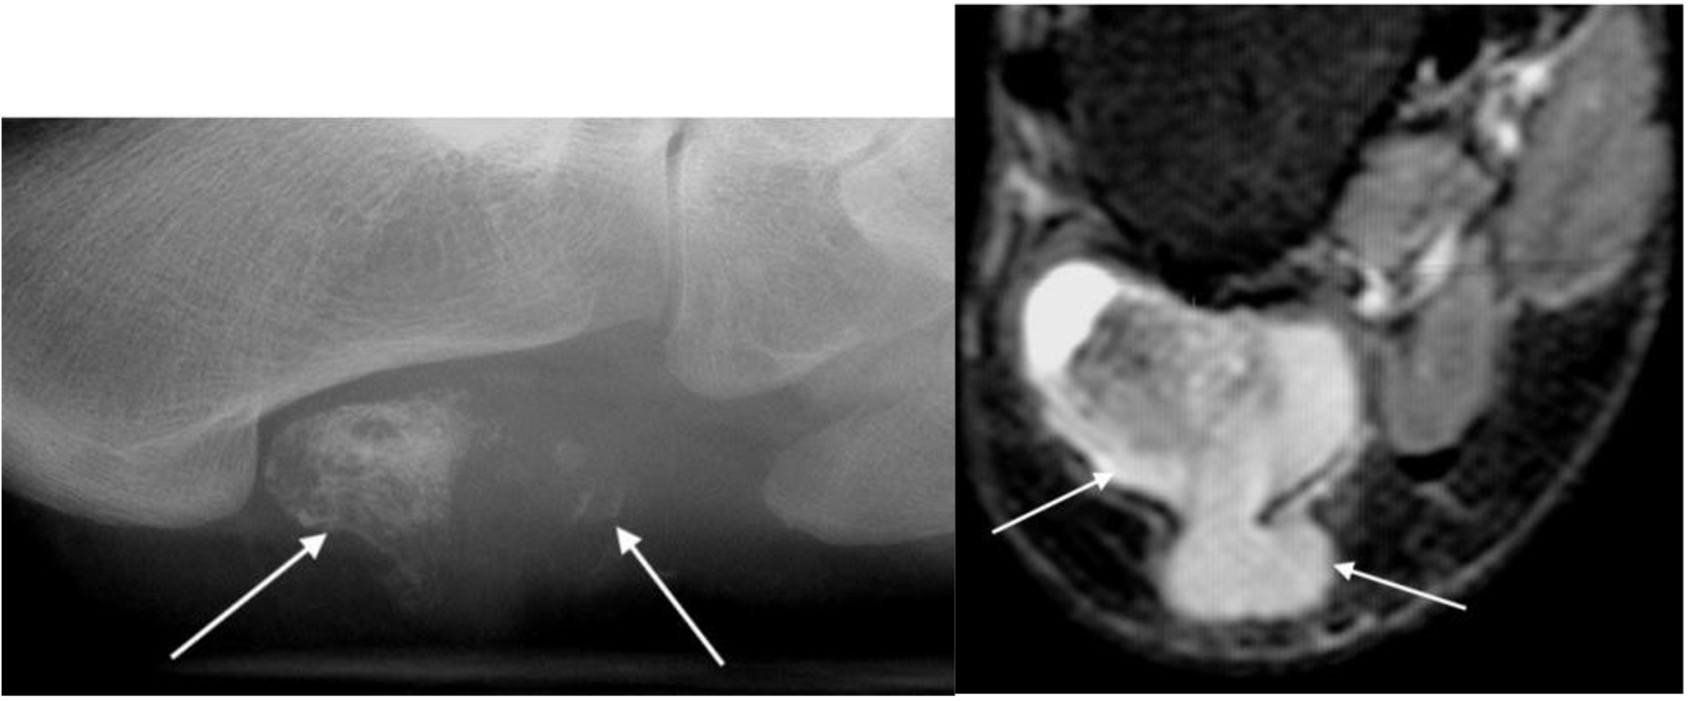

Synovial osteochondromatosis

- Occurs mainly in young or middle-aged adults

- Multiple metaplastic cartilaginous bodies form in the synovial membrane of a joint and become ossified

- Seen as multiple calcified intra-articular bodies, accompanied by a joint effusion

- In chronic cases, there may be pressure erosion of the periarticular bone

Synovial osteochondromatosis of the ankle joint with multiple intra-artcular ossific bodies (arrows)

Pigmented villonodular synovitis

- More recently called intra-articular tenosynovial giant cell tumour

- Most commonly seen in young adults

- Characterized by villous nodular proliferation of the synovium with haemosiderin deposition

- Dense periarticular soft tissue swelling with pressure erosion of the subarticular bone

- Joint space preserved until fairly late

- No calcification

- MRI useful to demonstrate the villous nodular synovial masses with low signal haemosiderin on all imaging sequences

PVNS with periarticular soft tissue swelling (arrowheads), bone erosion (arrow) and low signal synovial proliferation on MRI (arrows)